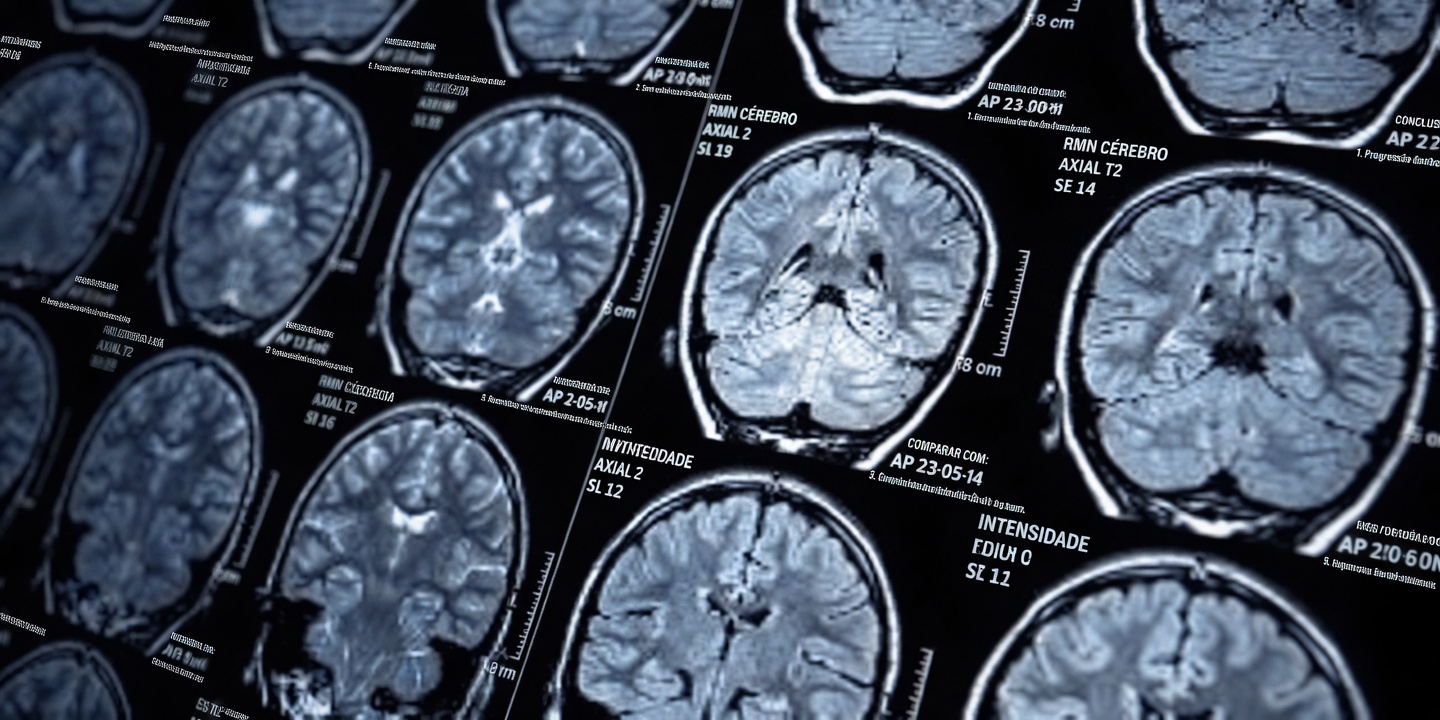

Os AVCs lacunares costumam atingir pessoas acima dos 60 anos de forma discreta: provocam pequenas lesões profundas no cérebro que, com o tempo, podem prejudicar o equilíbrio, a memória e a autonomia — muitas vezes sem nenhum “grande” sinal dramático. Um tropeço leve ou um momento de confusão pode parecer apenas “coisa da idade”, mas esses sinais de alerta de AVC lacunar podem se acumular, trazendo frustração, perda de confiança e dependência para atividades que antes eram simples.

O problema é que cada evento pode ser pequeno e passar despercebido. Mesmo assim, ao longo dos anos, pode haver dano em áreas como tálamo, gânglios da base e substância branca, afetando mobilidade, controle da bexiga, humor e funções executivas. Estudos populacionais apontam que esses sinais se tornam mais frequentes após os 60 — e entender o padrão ajuda você a conversar com o médico com mais objetividade, em vez de aceitar tudo como “normal”.